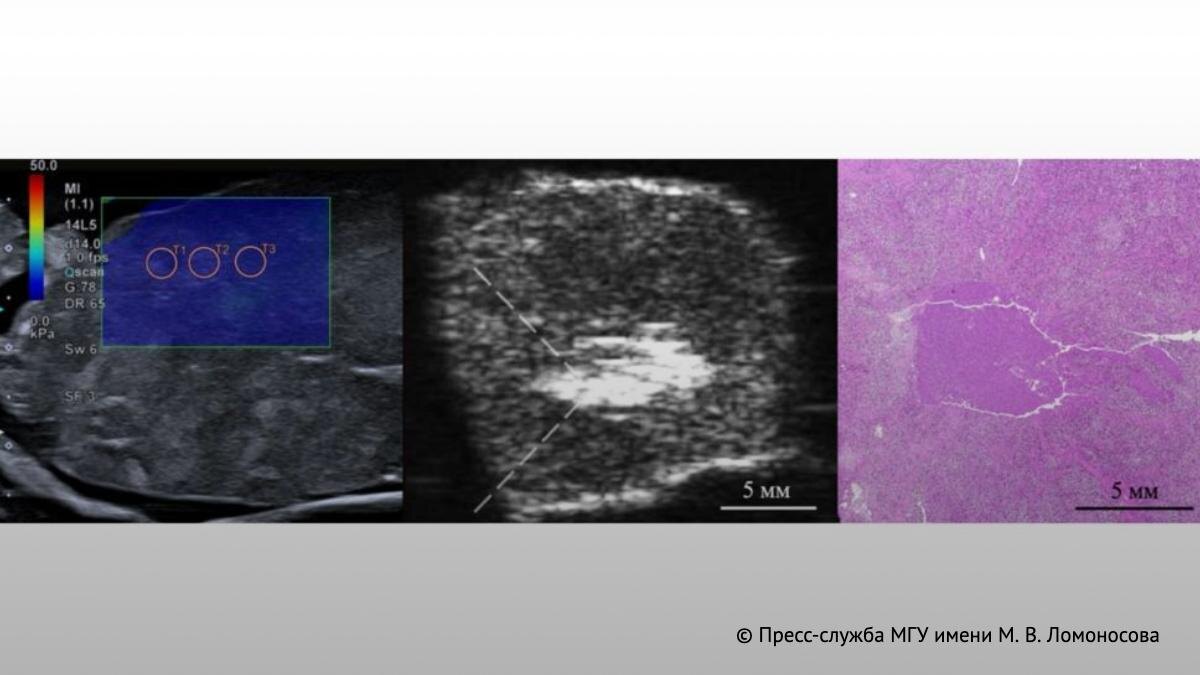

Фото: Пресс-служба МГУ имени М.В. Ломоносова  📷

Идея метода проста: фокусированная серия высокоамплитудных ультразвуковых импульсов миллисекундной длительности проходит через кожу и здоровые ткани и воздействует прямо на опухоль. Разрушение происходит не за счёт нагрева, а механически, через ударные фронты акустических волн. Здоровые ткани при этом остаются неповреждёнными. Гистологический анализ показал: опухолевые клетки полностью разрушаются, при этом граница между повреждённой и здоровой тканью не превышала 200 микрометров.